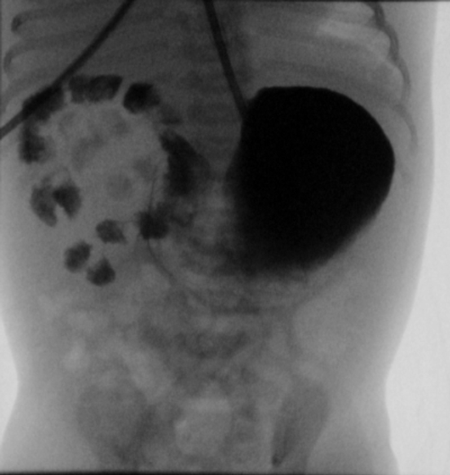

A full-term 2610g male neonate was admitted to the intensive care unit (NICU) with an antenatal history significant for a “double bubble” detected during the second trimester ultra sound examination (Fig. 1). A presumed diagnosis of duodenal stenosis/atresia was made with further karyotyping and anomaly scan showing no abnormalities. The antenatal imaging performed in the third trimester re-confirmed the findings of a double-bubble with no other anomalies being identified. Born at 38 +2/7 weeks, with APGAR scores of 7 and 9, the neonate had mild fullness of the right upper quadrant on clinical exam but no palpable mass. A supine abdominal x-ray revealed a dilated small bowel loop in the right upper quadrant with distal bowel gas, which was interpreted as a possible mega duodenum due to obstruction at that site consistent with the antenatal “double bubble” finding (Fig. 2). Patient then underwent an upper gastrointestinal series (UGI), which initially revealed no evidence of gastric outlet and duodenal obstruction or malrotation. However, subsequent delayed films showed of a space-occupying lesion in the right upper quadrant with a characteristic displacement of small bowel loops. Its subsequent opacification on delayed films was suggestive of a duplication cyst (Fig. 3). No evidence of bowel obstruction was seen. A post-natal ultrasound was not considered necessary in view of the findings on the UGI series.

Figure 2: Neonatal flat plate, large gas bubble in RUQ suggestive of partial duodenal obstruction |